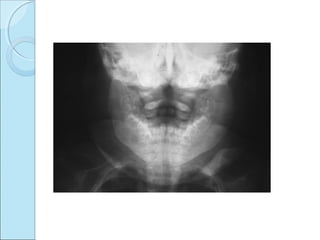

RADIOGRAPHIC FINDINGSRADIOGRAPHIC FINDINGS

 Juxta articular defects

transradiant subcortical band.

collapse of articular cortex.

sequestration of articular cortex.

secondary osteoarthritis.